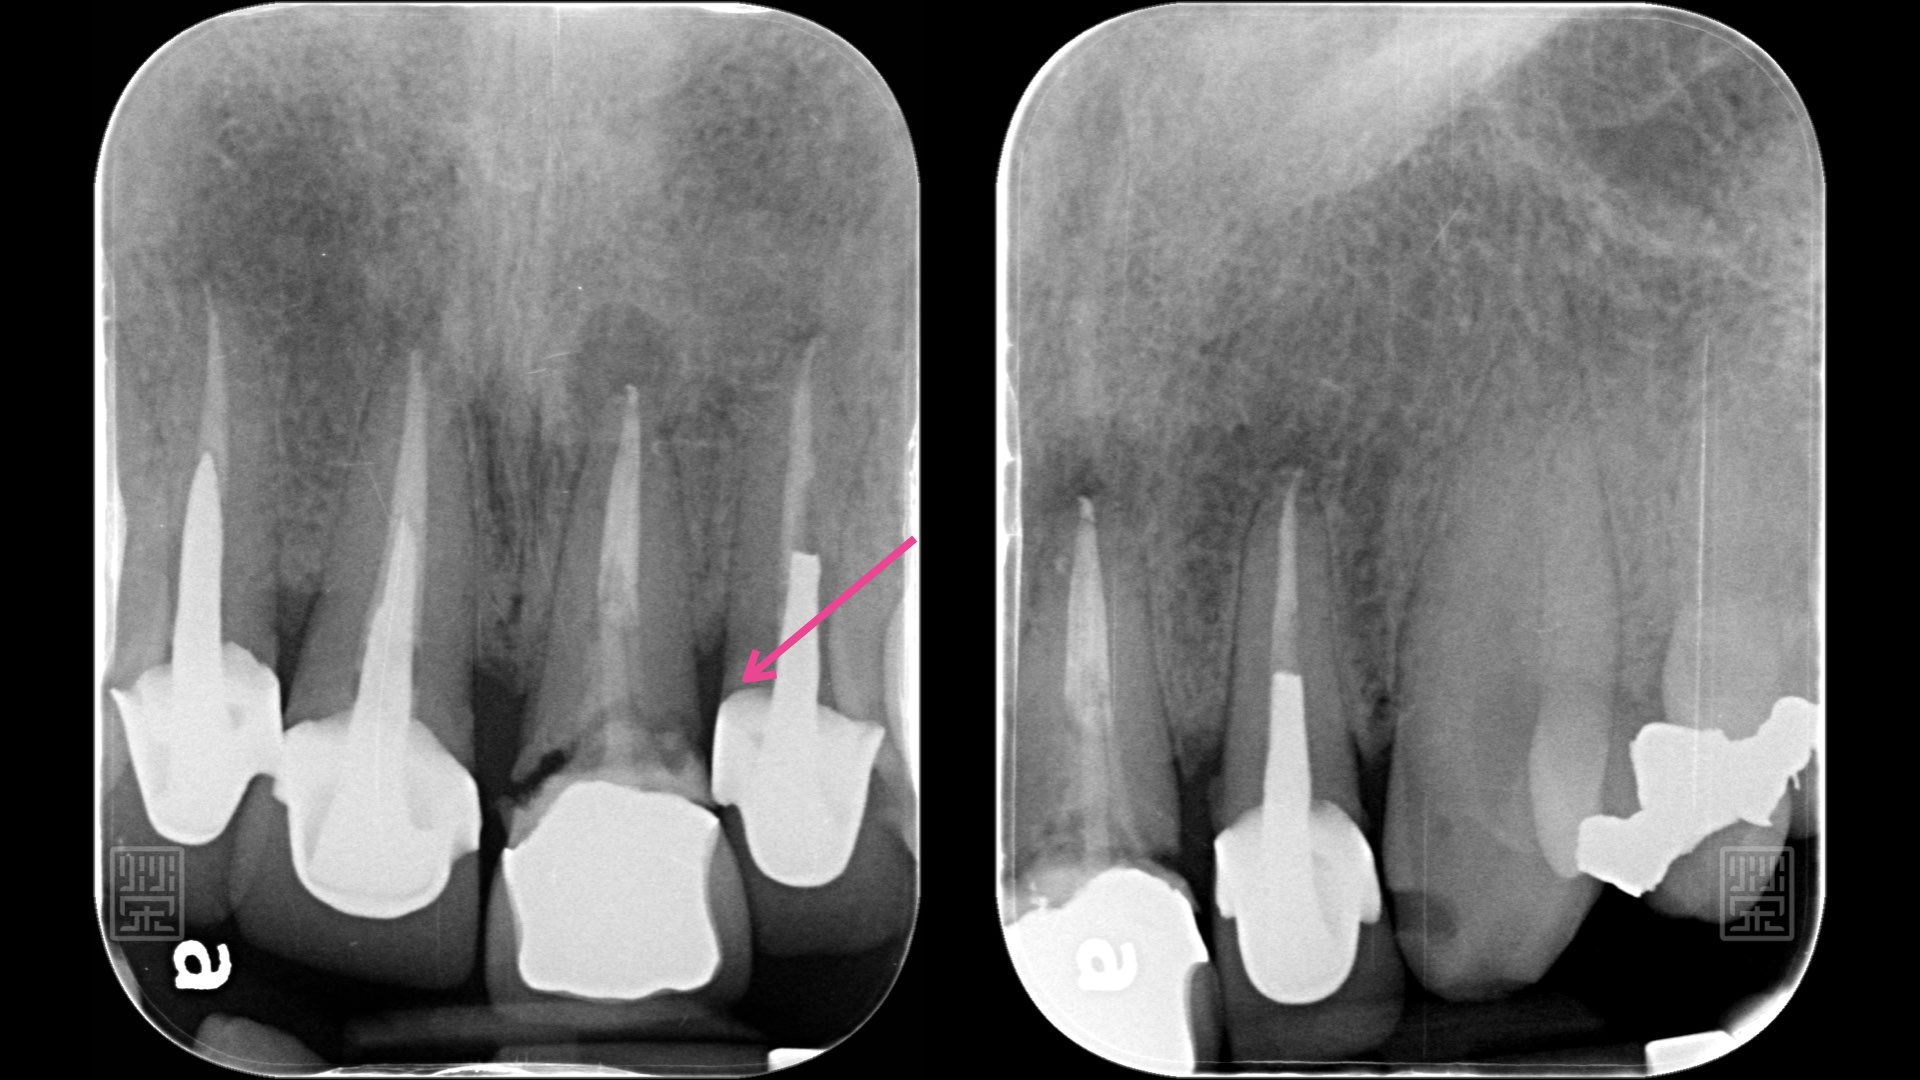

X光片明顯看到中門牙斷裂痕

斷層掃描發現中門牙與側門牙都有斷裂痕